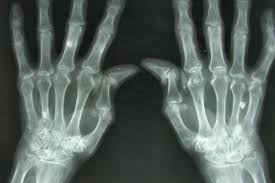

Normalde ince ve şeffaf olan eklem zarı (sinovyum), bu saldırı altında hızla kalınlaşmaya başlar. Damarlar kontrolsüzce çoğalır ve pannus adı verilen, saldırgan bir doku oluşur. Bu doku, adeta bir asit gibi kıkırdağı eritir ve kemiği kemirir. TNF-α, IL-1 ve IL-6 gibi sitokinler, yangını körükleyen moleküler yakıtlardır. Sonuç; sabahları kilitlenen, şişmiş ve yavaş yavaş şekil değiştiren eklemlerdir.

Simetrik Küçük Eklem Tutulumu: Sens. %60 - 80 Spe. %70 - 90 LR(+) ~3 -5. Olasılığı orta derecede artırır. Sabah Tutukluğu (>1 Saat): Sens. %75 - 85, Spe. %30 - 40 LR(+) ~1.5 Spesifik değildir ama varlığı değerlidir. Anti-CCP (ACPA): Sens. %67 - 80 Spe. %95 - 98 LR(+) 12 - 20 En güçlü kanıt. Olasılığı %90 üzerine taşır. Romatoid Faktör (RF): Sens. %60 - 70 Spe. %70 - 85 LR(+) 3 - 5. Destekleyicidir ancak tek başına yetersizdir. Erozyon (Radyografi): Sens. %45 - 50 Spe. %90 - 95 LR(+) ~8 Geç kalındığını ama tanının netliğini gösterir.